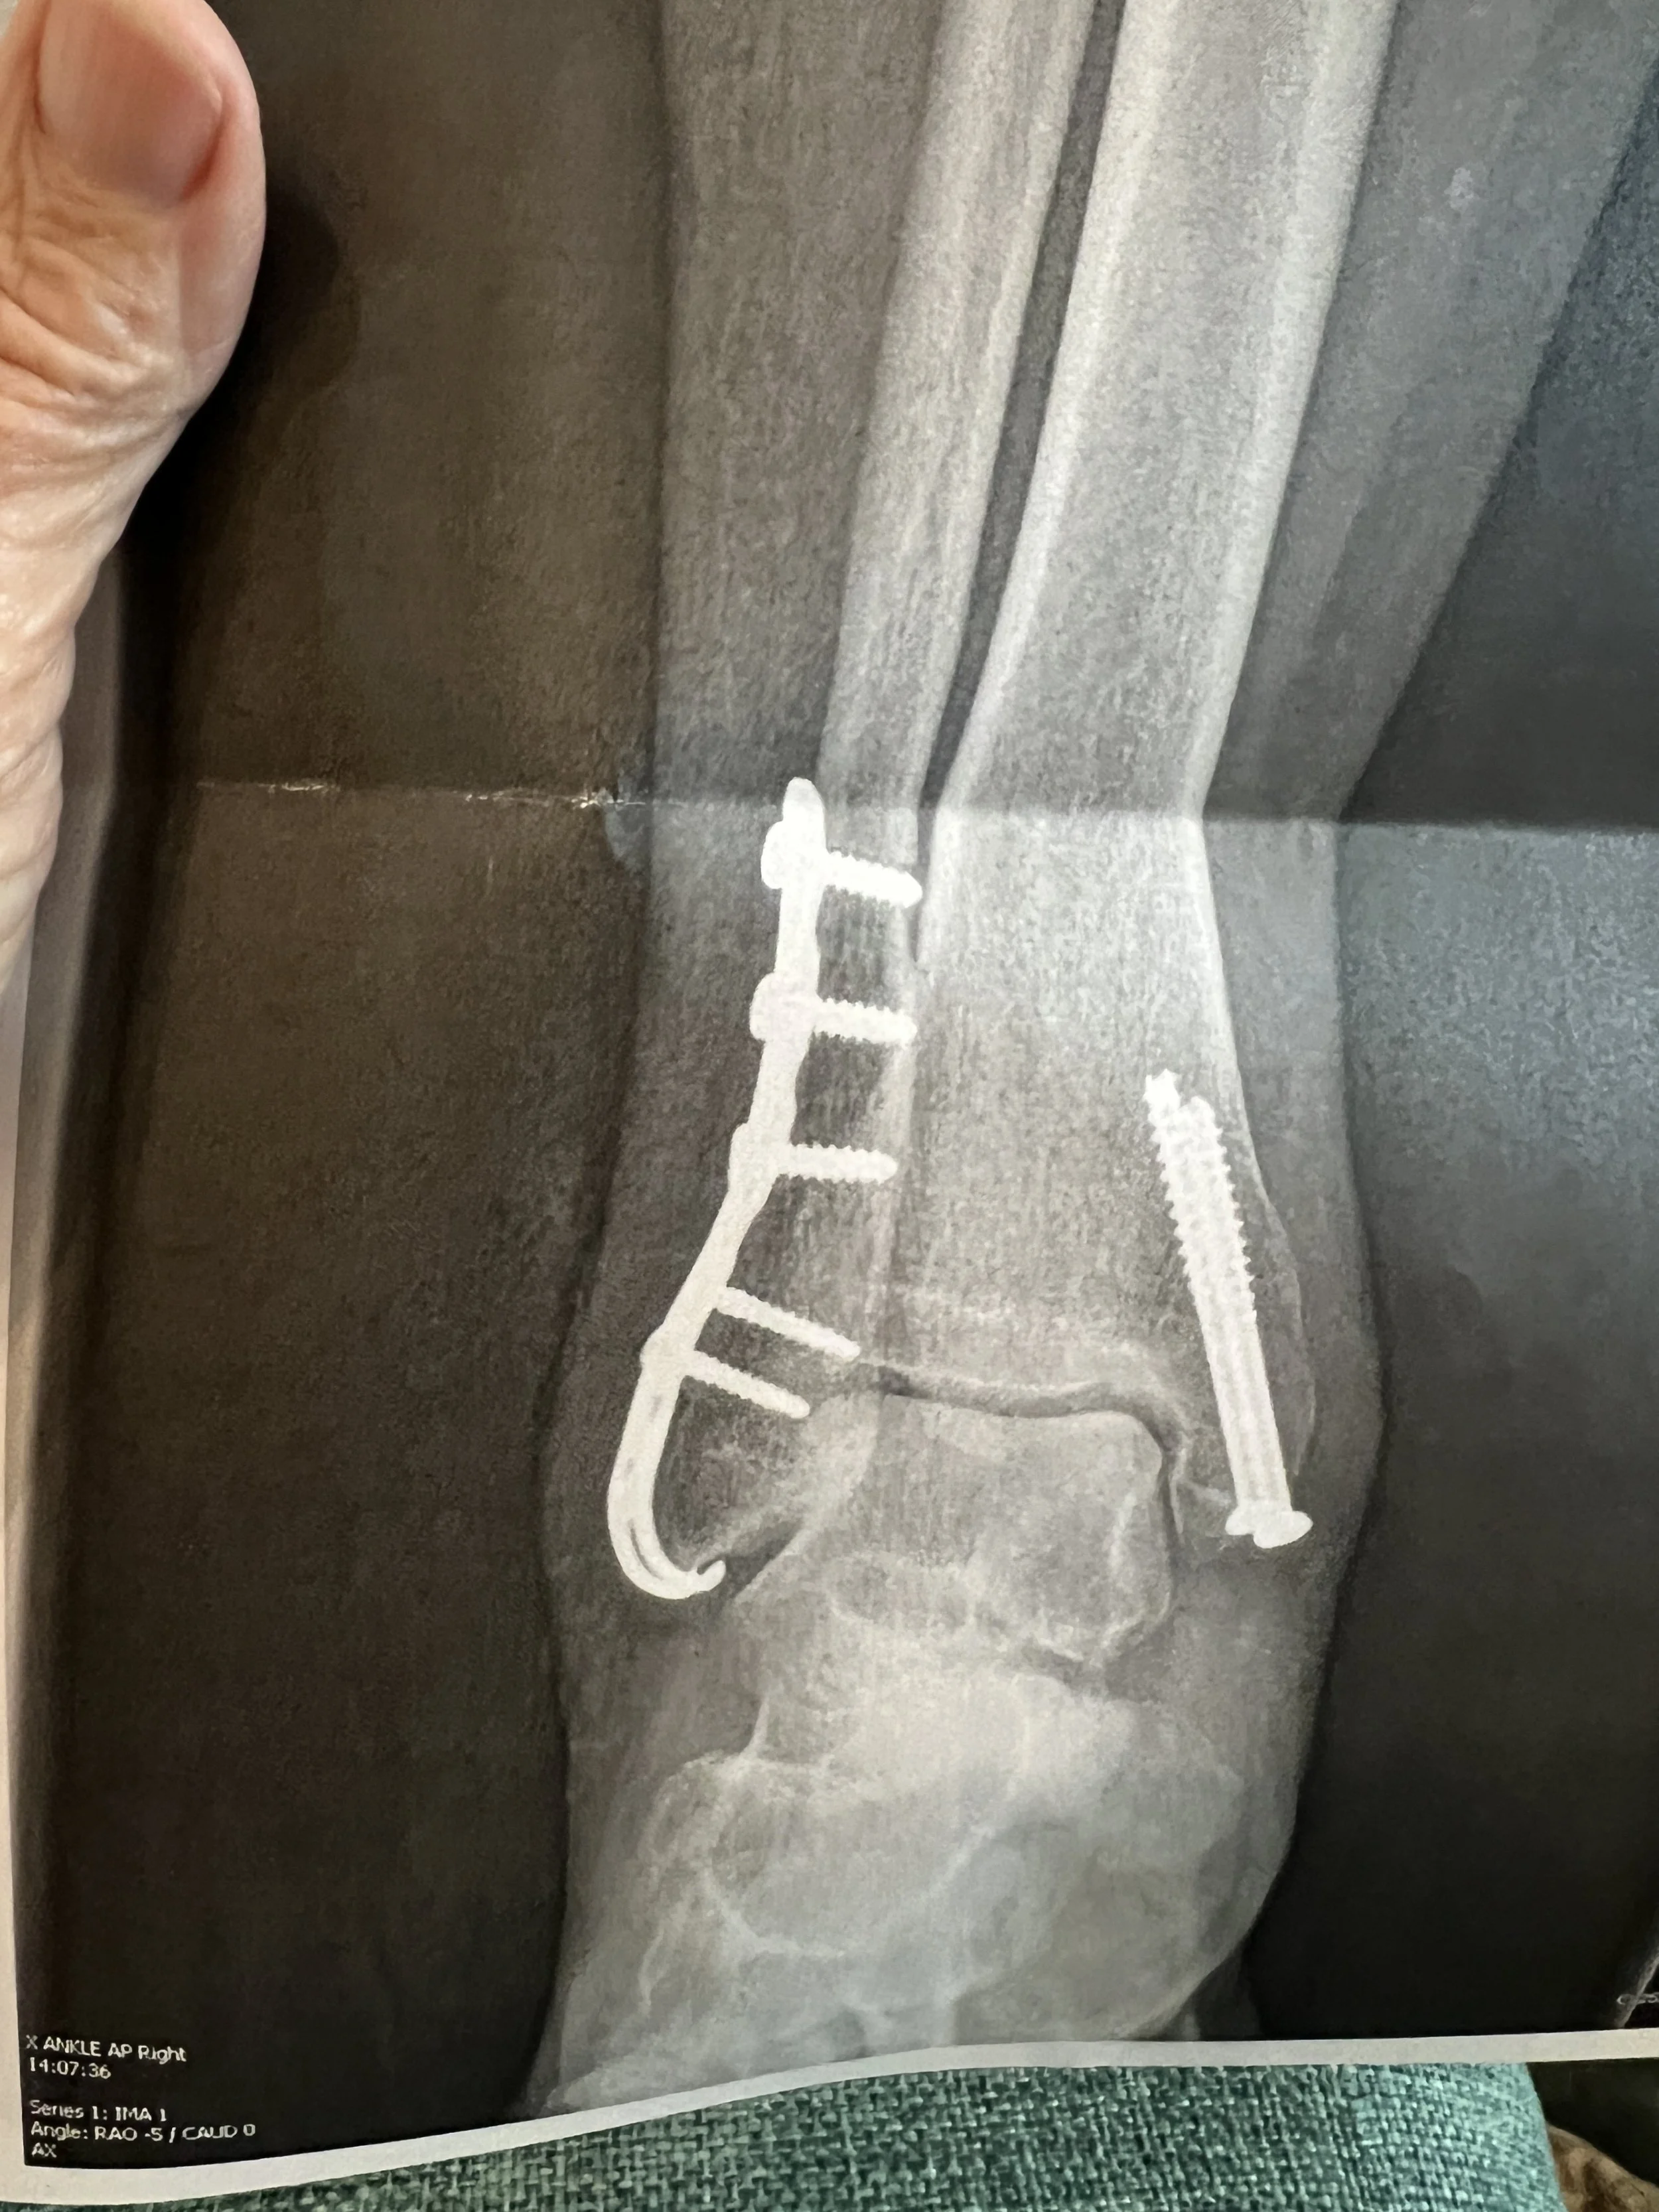

What does the procedure involve?

• Day surgery under general or regional anesthesia. Incisions are usually made over prior scars, implants are located, and plates/screws are removed. If a syndesmotic screw is removed, it’s often a small outpatient procedure. (Approach varies by implant and anatomy.) FootCareMD